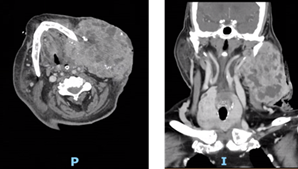

Ao apurar que na verdade não existia alergia ao contraste, repetiu TC cervical para melhor caracterização e eventual embolização da massa que revelou “extensa lesão expansiva infiltrativa, com expressão facial cervical superior à esquerda, com extensão ao espaço mastigador e ao espaço perifaríngeo e envolvendo a hemimandíbula. A lesão apresenta diâmetro máximo de 107 mm. A lesão é hipervascularizada - múltiplos voids vasculares, encontrando-se o pedículo alimentar na sua face medial” (Figs. 20 e 21).

Figs. 20 e 21 : TC cervical com contraste (corte axial e coronal) - Massa cervical esquerda hipervascularizada com extensão muscular e da hemimandíbula